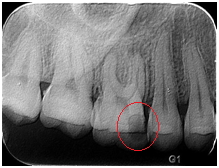

【根尖片】

◆磨牙龋齿

◆根管治疗完成后